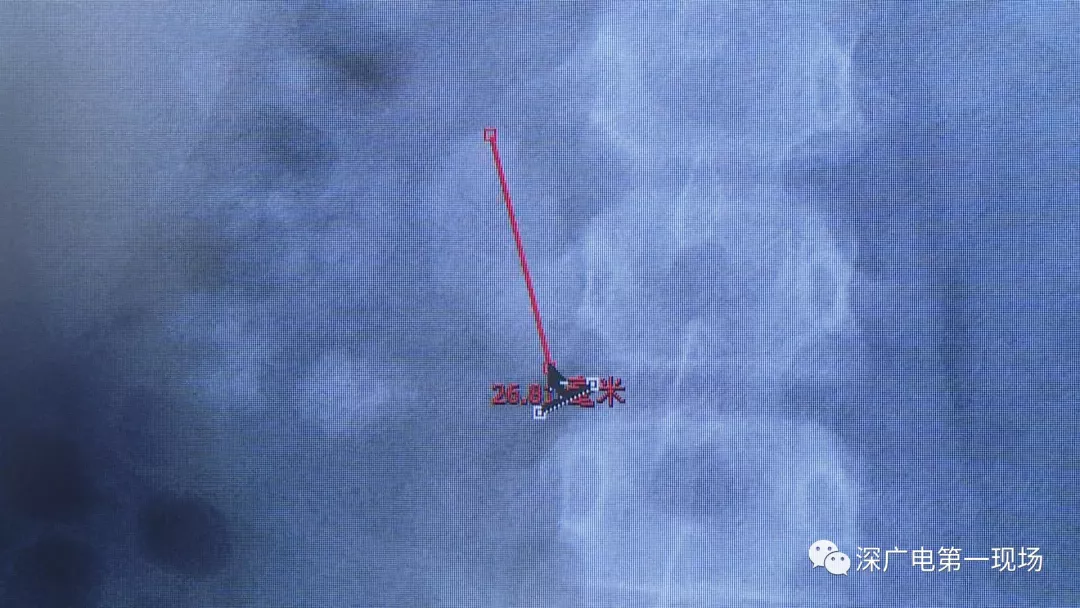

小軒這種情況,其中,最大的結(jié)石長約2.7厘米,寬約1.7厘米,體積堪比鵪鶉蛋,不但造成了尿路堵塞,還導(dǎo)致了右腎中度積水。